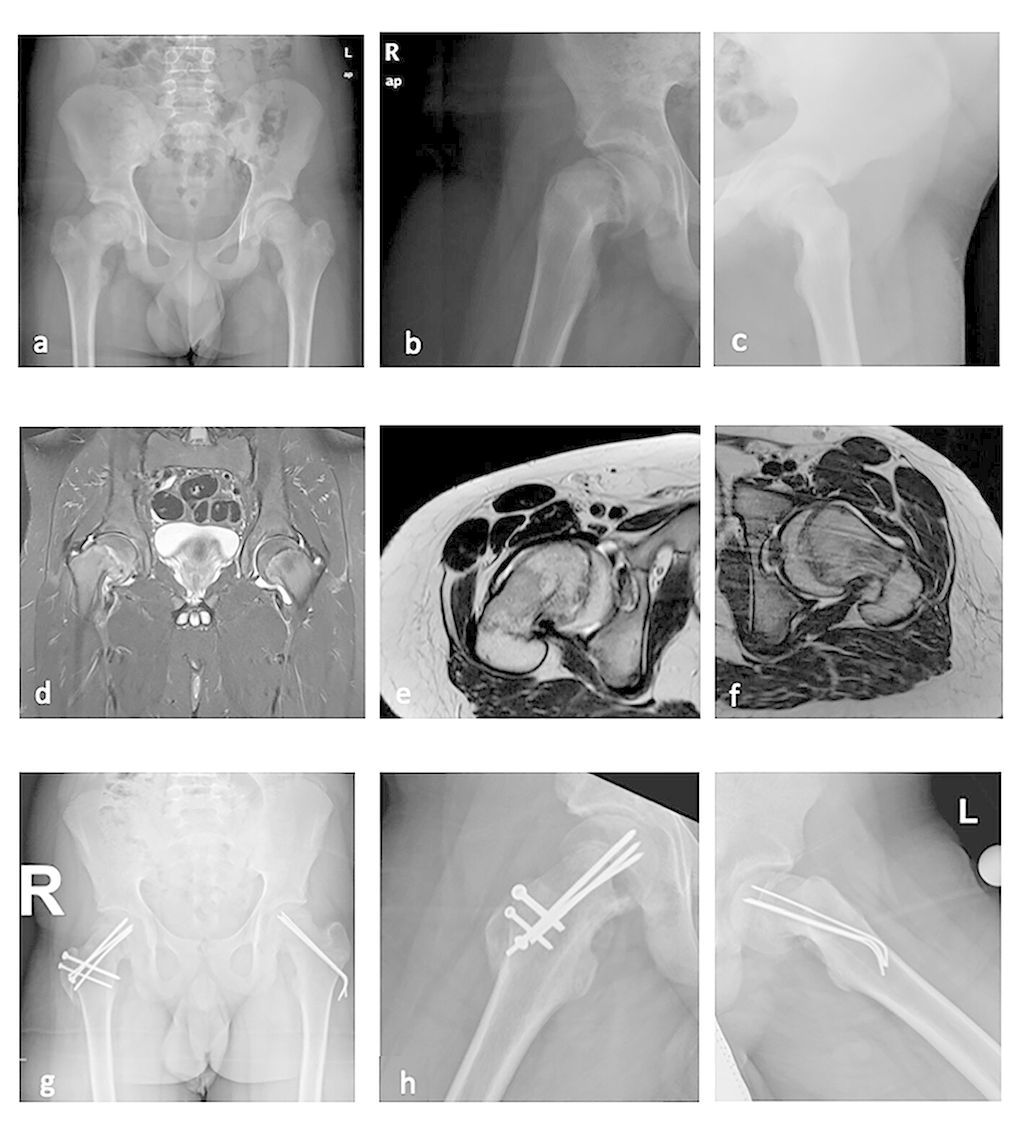

Abb. 2: Fallbeispiel: Adipöser 14-jähriger Patient mit beidseitiger ECF. Der Patient wurde akut wegen Gehunfähigkeit eingeliefert. Davor seit Wochen geringe Schmerzen, zunehmende Bewegungseinschränkung. Rechts (a, b, e) hochgradiger Abrutsch, akut auf chronisch (Kallusbildung vorhanden, die Epiphyse intraoperativ instabil). Links (a, c, f) mittelgradige ECF, chronisch, stabil. Klinisch keine Schmerzen, aber Bewegungseinschränkung. Rechts erfolgte die modifizierte Dunn-Osteotomie (g, h), links In-situ-Fixierung trotz erheblicher Restdeformität (g, i), da eine beidseitige Dunn-Osteotomie zu riskant gewesen wäre. Eine sekundäre Korrektur wird gegebenenfalls arthroskopisch erfolgen